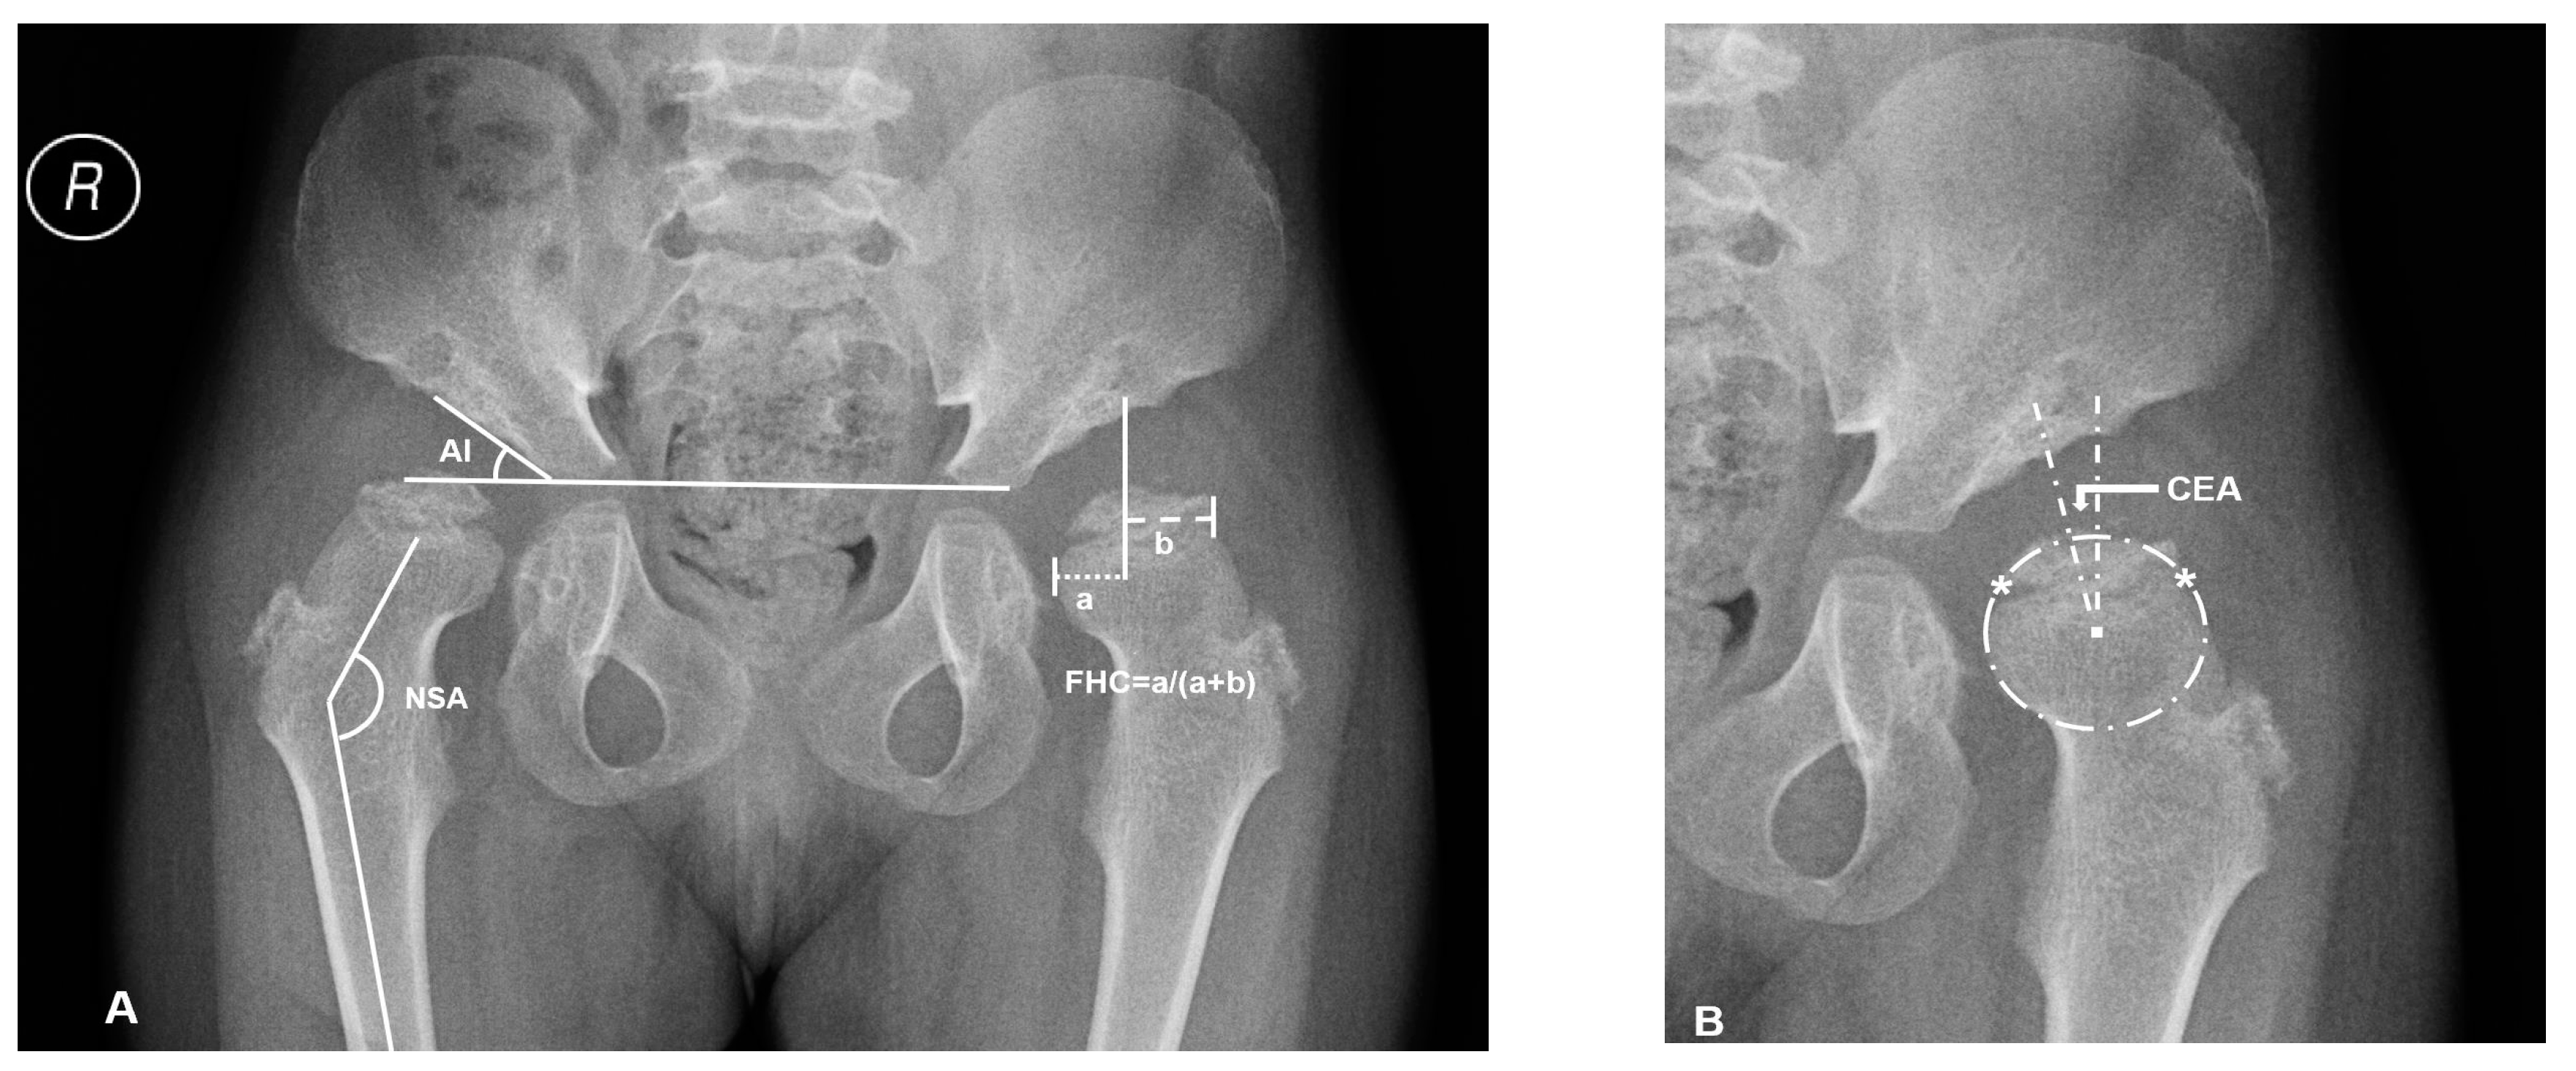

2.1. Radiographic Measurements and Analysis

| Range of Age(y) | Numbers of Patients | AI (°) | CAI (°) | CEA (°) | FHC (%) | NSA (°) | |||||

|---|---|---|---|---|---|---|---|---|---|---|---|

| MPS-IVA | NC † | MPS-IVA | NC† | MPS-IVA | NC ‡ | MPS-IVA | NC ‡ | MPS-IVA | NC § | ||

| 3 to 4 | 3 | 33 ± 2 | 19.89 | 19 ± 5 | 8.17 | −18 ± 10 | 23 | 29 ± 8 | 83–84 | 145 ± 8 | 145 |

| 4 to 5 | 6 | 33 ± 5 | 18.22 | 22 ± 6 | 7.9 | −26 ± 10 | 23 | 27 ± 18 | 79–84 | 143 ± 8 | 145 |

| 5 to 6 | 1 | 36 ± 1 | 18.51 | 24 ± 2 | 8.4 | −21 ± 4 | 23 | 30 ± 12 | 79–82 | 143 ± 4 | 142 |

| 6 to 7 | 2 | 35 ± 4 | 17.91 | 23 ± 1 | 8.19 | −9 ± 1 | 24 | 45 ± 8 | 80–82 | 147 ± 6 | 142 |

| 7 to 8 | 1 | 39 ± 1 | 18.25 | 25 ± 2 | 8.05 | −33 ± 1 | 26 | 9 ± 2 | 80–82 | 149 ± 5 | 142 |

| 8 to 9 | 4 | 40 ± 2 | 17.64 | 24 ± 4 | 8.15 | −16 ± 14 | 25 | 25 ± 9 | 81–82 | 150 ± 4 | 142 |

| 9 to 10 | 2 | 39 ± 6 | 16.40 | 23 ± 5 | 7.87 | −29 ± 5 | 25 | 18 ± 4 | 81 | 148 ± 4 | 138 |